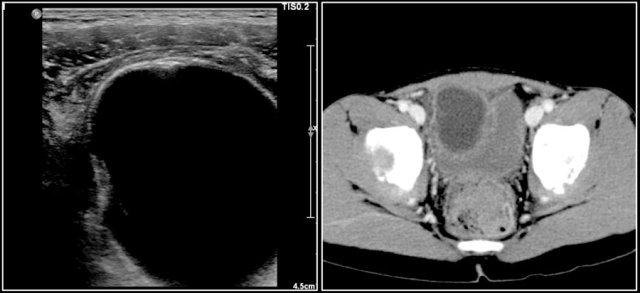

Here a CT-image of a 13-year-old girl presented with a lower abdominal mass.

It is a partly cystic, partly solid tumor with some calcifications.

The solid parts are inhomogeneous.

The tumor was resected and pathology showed a teratoma with malignant parts, with lymph node metastasis.